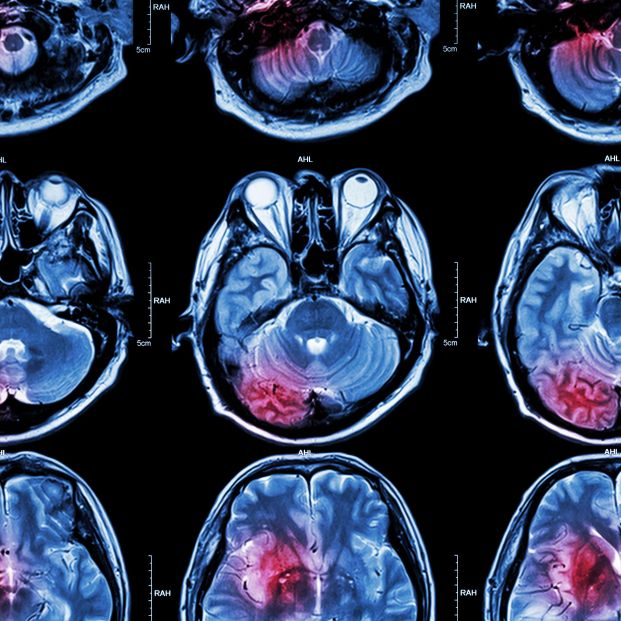

El glioblastoma, actualmente el tumor cerebral más agresivo y frecuente, está cada vez más cerca de topar con un tratamiento eficaz. El último avance llega desde el Vall d'Hebron Institut d'Oncologia (VHIO), donde un grupo de investigadores ha logrado crear un nuevo fármaco inmunológico eficaz que ya se está probando en humanos, según informaron en un comunicado.

Los glioblastomas son los tumores del sistema nervioso central más comunes y letales en adultos. Hasta ahora, sin embargo, no existe una inmunoterapia contra este tipo de tumor cerebral.